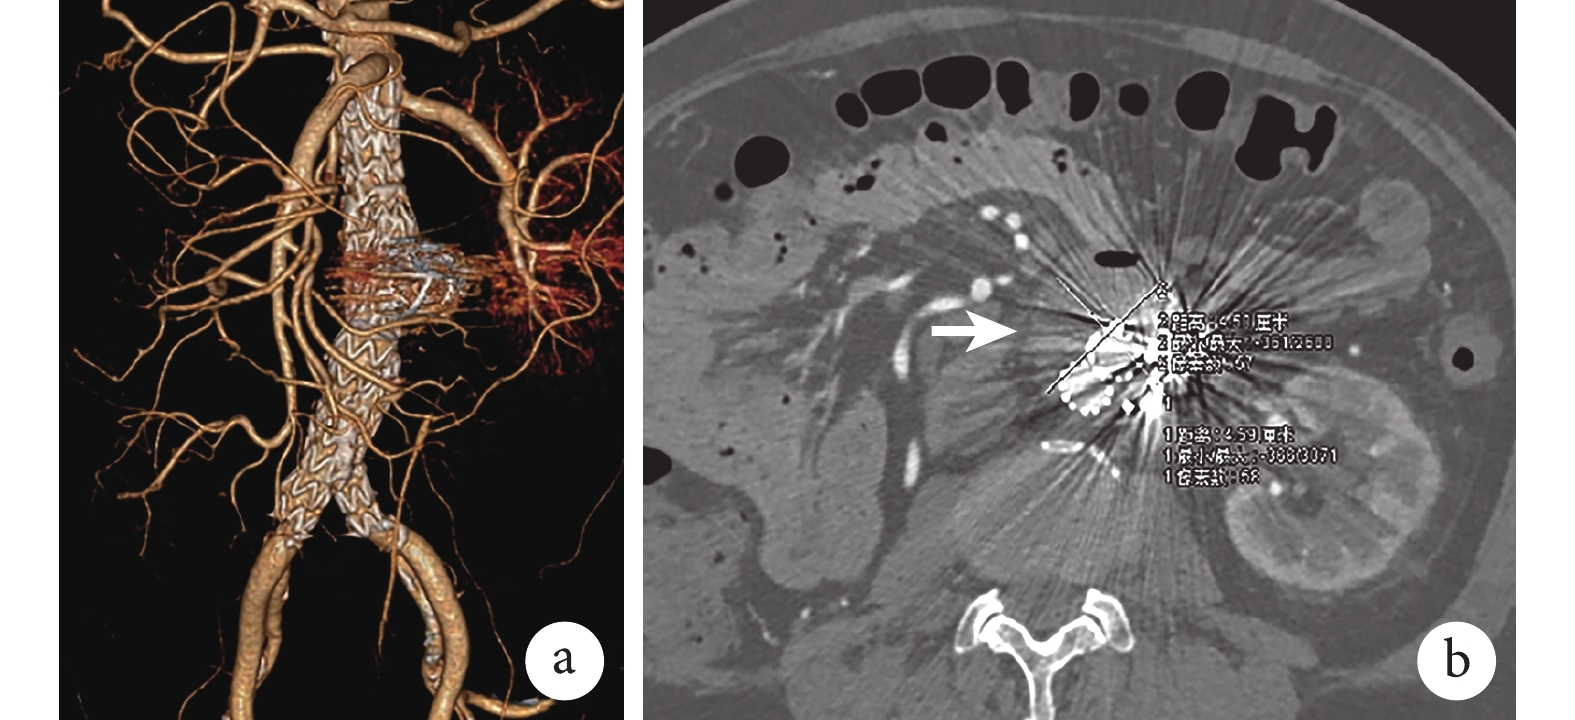

術前CT血管三維重建(computerized topographic angiography,CTA)顯示:腎下腹主動脈直徑約21 mm,瘤頸長30 mm;腎下腹主動脈瘤樣擴張、最大直徑約5 cm,瘤體累及腹主動脈分叉部;左側髂總動脈直徑為11 mm,長度為32 mm;右側髂總動脈直徑為13 mm,長度為30 mm(圖1a、1b)。IMA發自瘤體,直徑約4 mm(圖1c);3對通暢LA,其直徑均超過2 mm(圖1d~1f)。經MIMICS v21.0醫學影像控制系統測量,動脈瘤體積約為300 cm3。冠狀動脈CT檢查提示冠狀動脈支架植入術后,左右冠狀動脈中度狹窄;心臟彩超檢查顯示主動脈瓣輕度反流,射血分數為55%;胸部CT檢查提示雙肺慢性炎癥。

a:術前腹主動脈CTA圖像,可見腎下型腹主動脈瘤;b:腹主動脈瘤最大直徑約5 cm(白箭);c:IMA通暢,直徑約4 mm(白箭);d~f:3對通暢LA,直徑均超過2 mm(白箭)